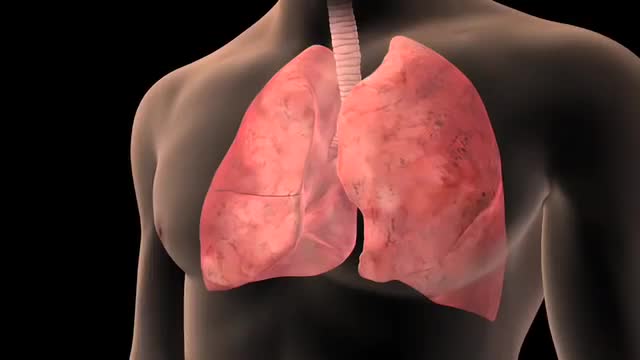

Lung Cancer

Lung cancer is a type of cancer that begins in the lungs. Your lungs are two spongy organs in your chest that take in oxygen when you inhale and release carbon dioxide when you exhale. Lung cancer is the leading cause of cancer deaths in the United States, among both men and women. Lung cancer claims more lives each year than do colon, prostate, ovarian and breast cancers combined. People who smoke have the greatest risk of lung cancer. The risk of lung cancer increases with the length of time and number of cigarettes you've smoked. If you quit smoking, even after smoking for many years, you can significantly reduce your chances of developing lung cancer.